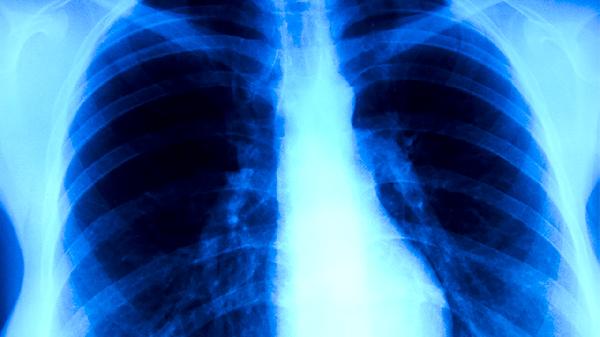

胸部CT檢查能更清晰顯示肺部細(xì)微病變,對(duì)早期肺結(jié)核、支氣管內(nèi)膜結(jié)核等診斷價(jià)值較高。高分辨率CT可發(fā)現(xiàn)X線難以顯示的微小病灶,評(píng)估病變范圍和活動(dòng)性,但輻射劑量相對(duì)較大且費(fèi)用較高。